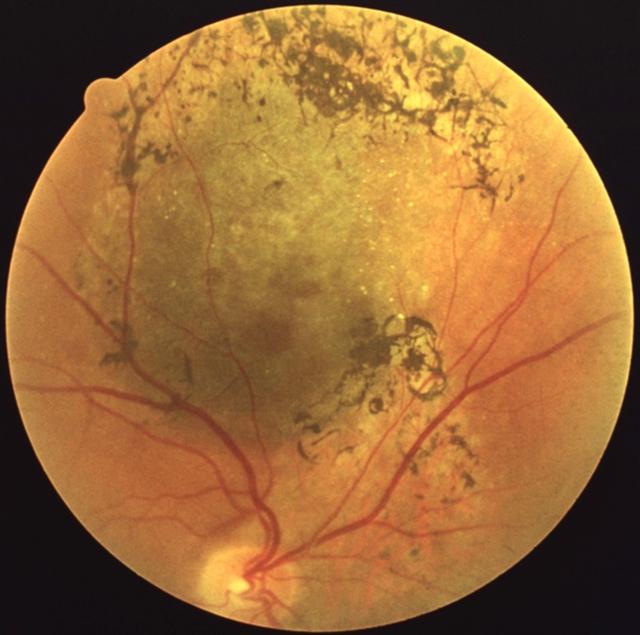

Рис. 9. Меланома собственно сосудистой оболочки: видны темно-серая проминирующая опухоль с оранжевыми полями в центральной части и пигментацией по периферии.